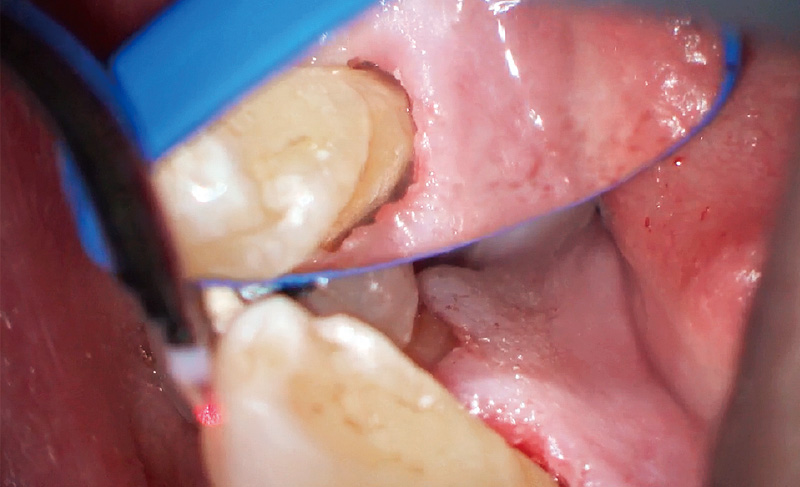

基本的に痛くなってからしか来ない患者の典型的症例(図3)。残存している下顎右側犬歯と第一小臼歯臼歯間のサイナストラクト発症により来院。側枝からの感染による歯髄壊死も考えられたため、ガッタパーチャを挿入後に、デンタル撮影にて部位特定。歯周病急性症状改善後、歯周ポケット測定を行うと舌側中央に8mmのポケットを確認した(図4)。

プリセットモード「歯石除去」にてS600Tのチップを用いてディープスケーリング5)を行った(図5)。縁下内部をEr:YAGレーザーで照射、スケーリングしていくと、内部から縁下歯石がポケット外へ飛び出してくる。S600Tを用いることにより、ポケット内縁上皮も掻爬され健全な根面を得ることができた(図6)。